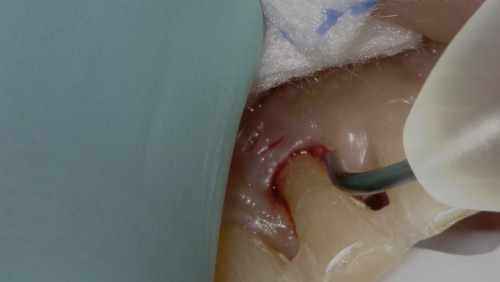

Compare this to use of the Gemini laser. We can set the power setting of the laser using the preset power settings for “Troughing” (Fig. 2) at 1.1 watts. The pre-initiated tip (pigment on the laser fiber converts some of the laser energy to photothermal energy) is placed into the sulcus to ablate the soft tissue, which creates a clear separation of the soft tissue from the tooth margin and achieves instant hemostasis (Fig. 3). We then have no need to wait and can immediately take the impression (Fig. 4). I consider this alone as priceless in my day-to-day practice.

Fig. 1 Fig. 2 Fig. 3